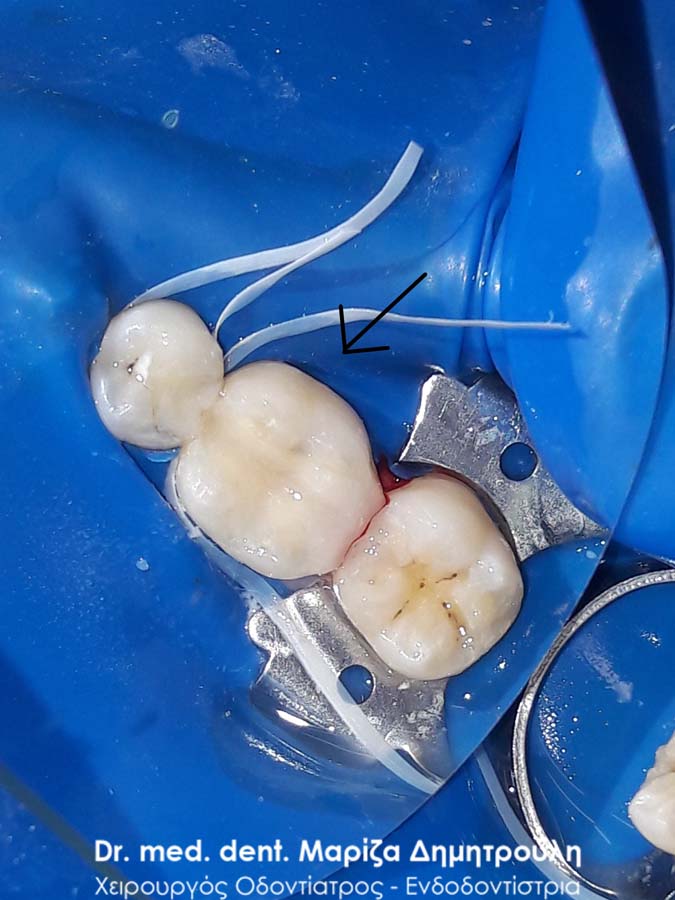

Εικόνα των δοντιών μετά την αφαίρεση των μαύρων σφραγισμάτων

Εικόνα των δοντιών μετά την αφαίρεση των σφραγισμάτων αμαλγάματος